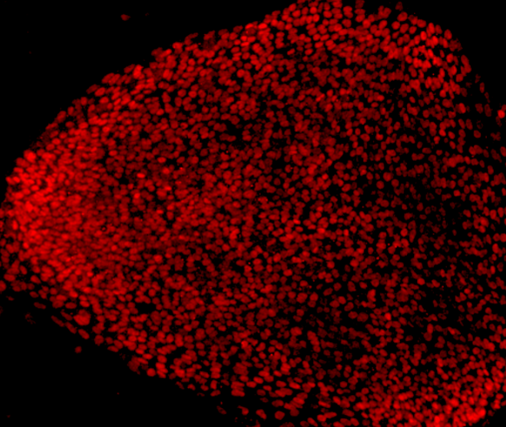

日本研究人员日前宣布,通过动物实验发现一种红色的食用色素对治疗恶性胶质瘤有效,今后有望在此基础上开发出新的治疗药物...